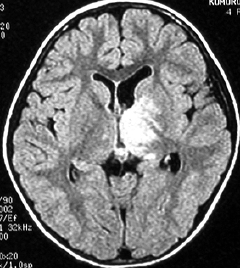

これは4歳の女の子の左の視床にできた乏突起膠腫です。コンピュータガイドの定位脳手術という方法で生検術をしました。病理像はやはり高分化型なのですが,大きくなると困る場所なので,半定位放射線治療を46グレイあてました。MRIの左側は放射線治療前,右側は放射線治療6年後のものです。腫瘍は縮小したままで再燃せず,10年以上経過しますが元気に学校へ行っています。視床下部へ照射が入ったので思春期早発を生じました。